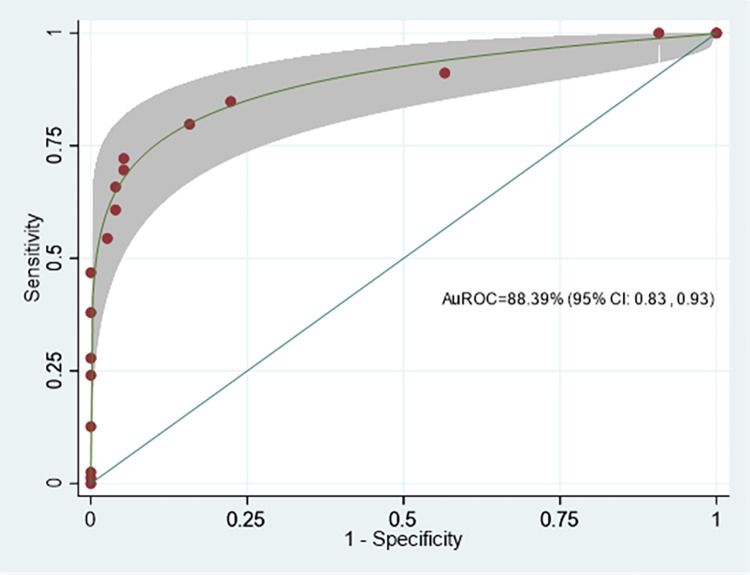

Model performance

The model discrimination performance is demonstrated by the ROC curve of the Difficult CBD stone score (DCSS) model, shown in Fig 2. The area under the receiver operating characteristic curve (AuROC) of the DCSS model revealed an affinity for prediction of 88.39% (95% CI: 0.83, 0.93).

The Hosmer-Lemeshow goodness-of-fit test for the DCSS model also revealed insignificant results (p-value = 0.625). In this data set, the DCSS model proved suitable for predicting EPLBD requirements.

Internal validation was performed by the bootstrap sampling method with 500 replications, which showed constant AuROC 0.884 (95%CI 0.830, 0.938) with model optimism adjusted at AuROC 0.883 (95%CI 0.833, 0.942). The analysis showed acceptable predictive performance.

The ROC curve and AuROC of the DCSS model were compared using the added value concept to an intelligent difficulty scoring and assistance system (DSAS) for endoscopic treatment of common bile duct (CBD) stones that was proposed by Huang et al. [ref. 13] (Fig 5.) The DCSS model’s ability to predict the required EPLBD was 88.78%, which increased from the ability to predict the required EPLBD of DSAS was 46.48% (p <0.001).